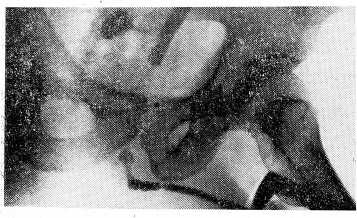

21/Ш 1977 г. поступил в клинику для дальнейшего лечения. В результате встречной уретрографии выявлена стриктура на всем протяжении мочеиспускательного канала (рис. 1). При экскреторной урографии не обнаружено патологии. 5/IV 1977 г. выполнена операция Михаловского на висячем отделе уретры, послеоперационный период протекал гладко. 21/IV 1977 г. М. выписан для амбулаторного наолюдения.

Рис. 1. Встречная уретрограмма больного М. до оперативной коррекции стриктуры уретры. Пениальный отдел равномерно сужен, имеются множественные четкообразные сужения от членомошоночного угла до простатического отдела уретры.